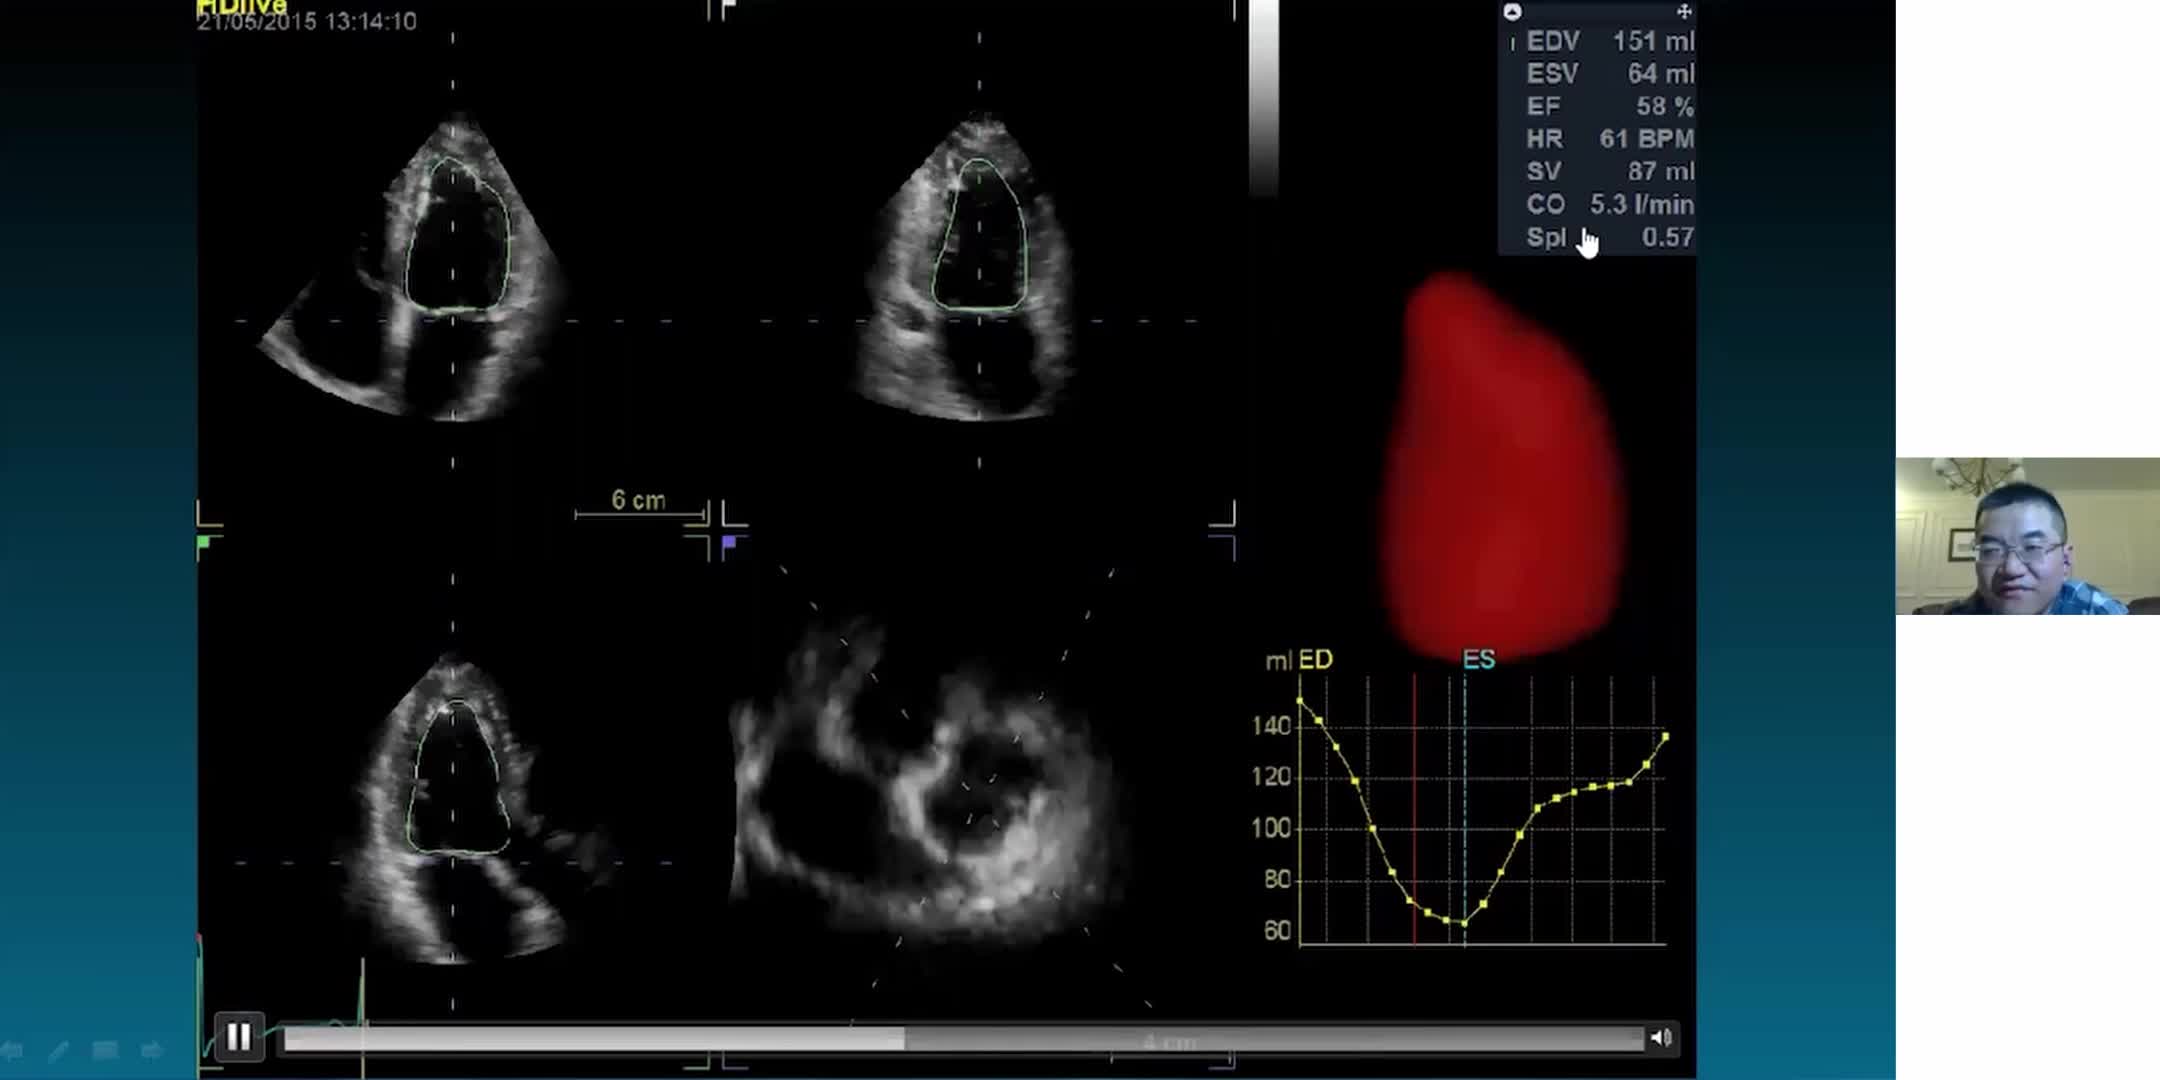

左室定量分析与超声诊断在休克评估中的应用

高级心脏超声评估技术详解